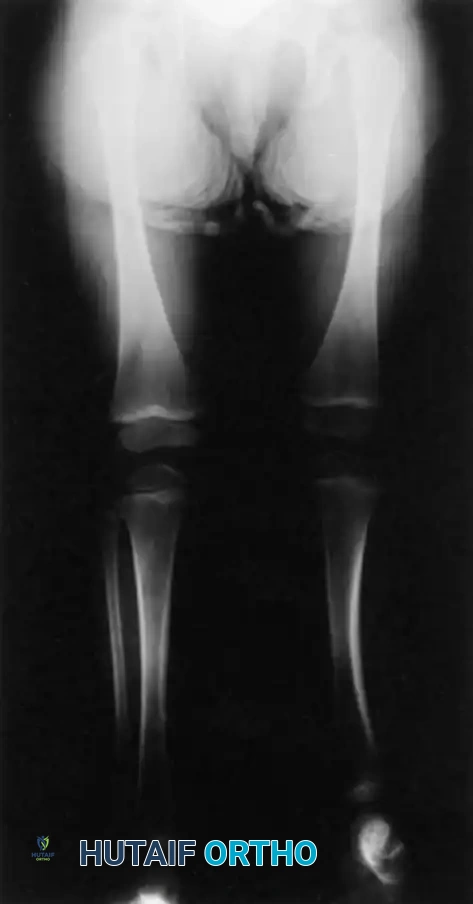

This condition represents a broad spectrum of deformities, ranging from the total absence of the tibia (the most severe form) to mild hypoplasia of the tibia (the least severe form). The incidence is exceedingly rare, estimated at one in 1 million live births, and the condition presents bilaterally in approximately 30% of affected patients.

Clinically, the involved leg is significantly shortened. The fibular head is often palpable, particularly if it is proximally displaced into the popliteal fossa. The foot is typically held in severe, rigid equinovarus, and the hindfoot is profoundly stiff.

In older children, the proximal tibial anlage may be palpable upon deep clinical examination, even if it is not radiographically visible. The knee is generally flexed, and in more severe deformities, profound quadriceps insufficiency causes an absolute lack of active knee extension.

- Type 2 Deformity: A proximal tibia of varying size is present and ossified at birth. The fibula is usually normal in size, but the fibular head is proximally dislocated.

- Type 3 Deformity: The proximal tibia is not radiographically visible, but the distal tibial epiphysis is present. This is an exceptionally rare variant. The distal femoral epiphysis is usually well-formed, but the upper end of the fibula is proximally dislocated, leading to profound knee instability.

- Type 4 Deformity: The tibia is shortened, and there is proximal migration of the fibula with distal tibiofibular diastasis. This rare deformity is also referred to as congenital diastasis of the ankle joint. The distal tibial epiphysis may be entirely absent.